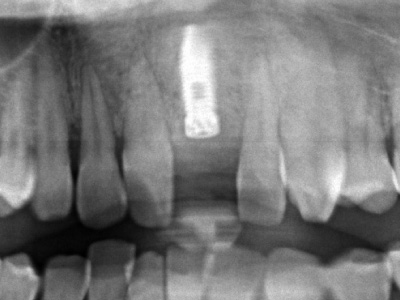

シミュレーションソフトを用いて正しいポジションにインプラントを埋入。

インプラントは骨の中に入るようにできるだけ細いものを使用していますが、それでも骨造成は必要です。

この時点では、歯と歯の間の「歯間乳頭」と呼ばれる歯茎が不足しているため隙間が空いており、インプラントの被せ物がいかにも人工物のように感じるため、審美的な仕上がりとはいえない。

インプラント周りに骨造成も実施しました。